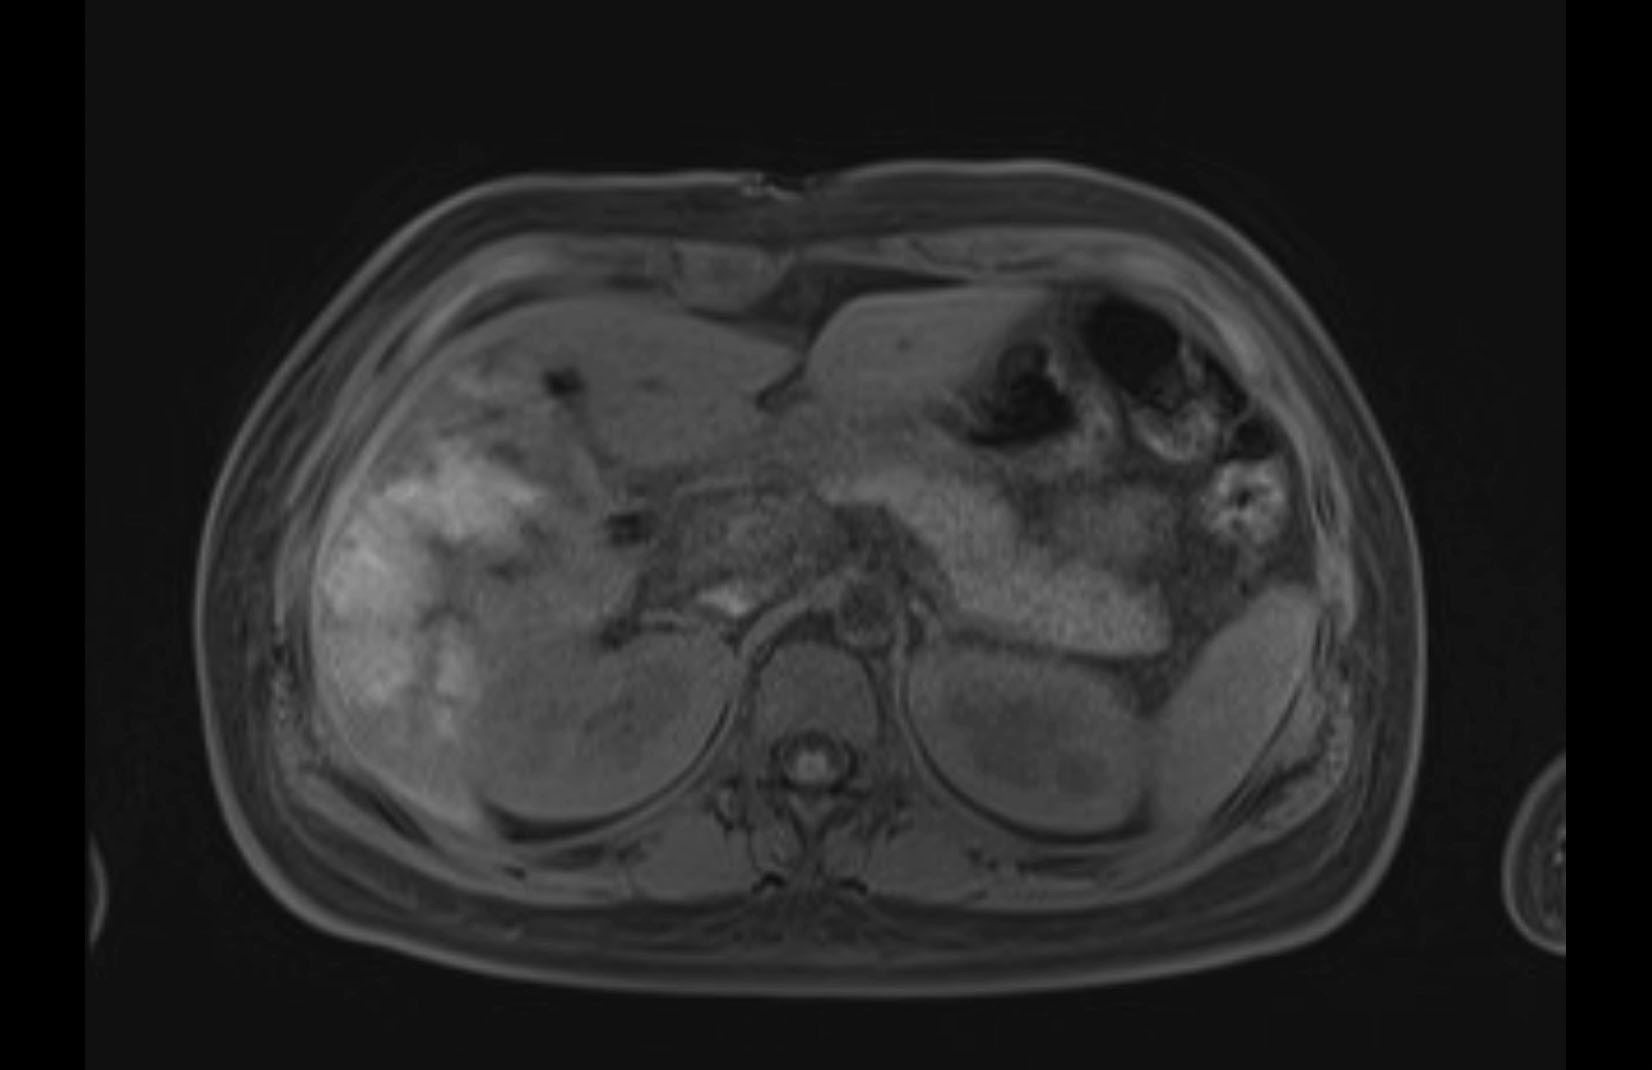

Imaging Analysis

Look through the patient's CT scan to identify any areas of concern for the necessary procedure.

MRI T1

MRI T2

Based on initial findings, which issue(s) would you be most concerned about?